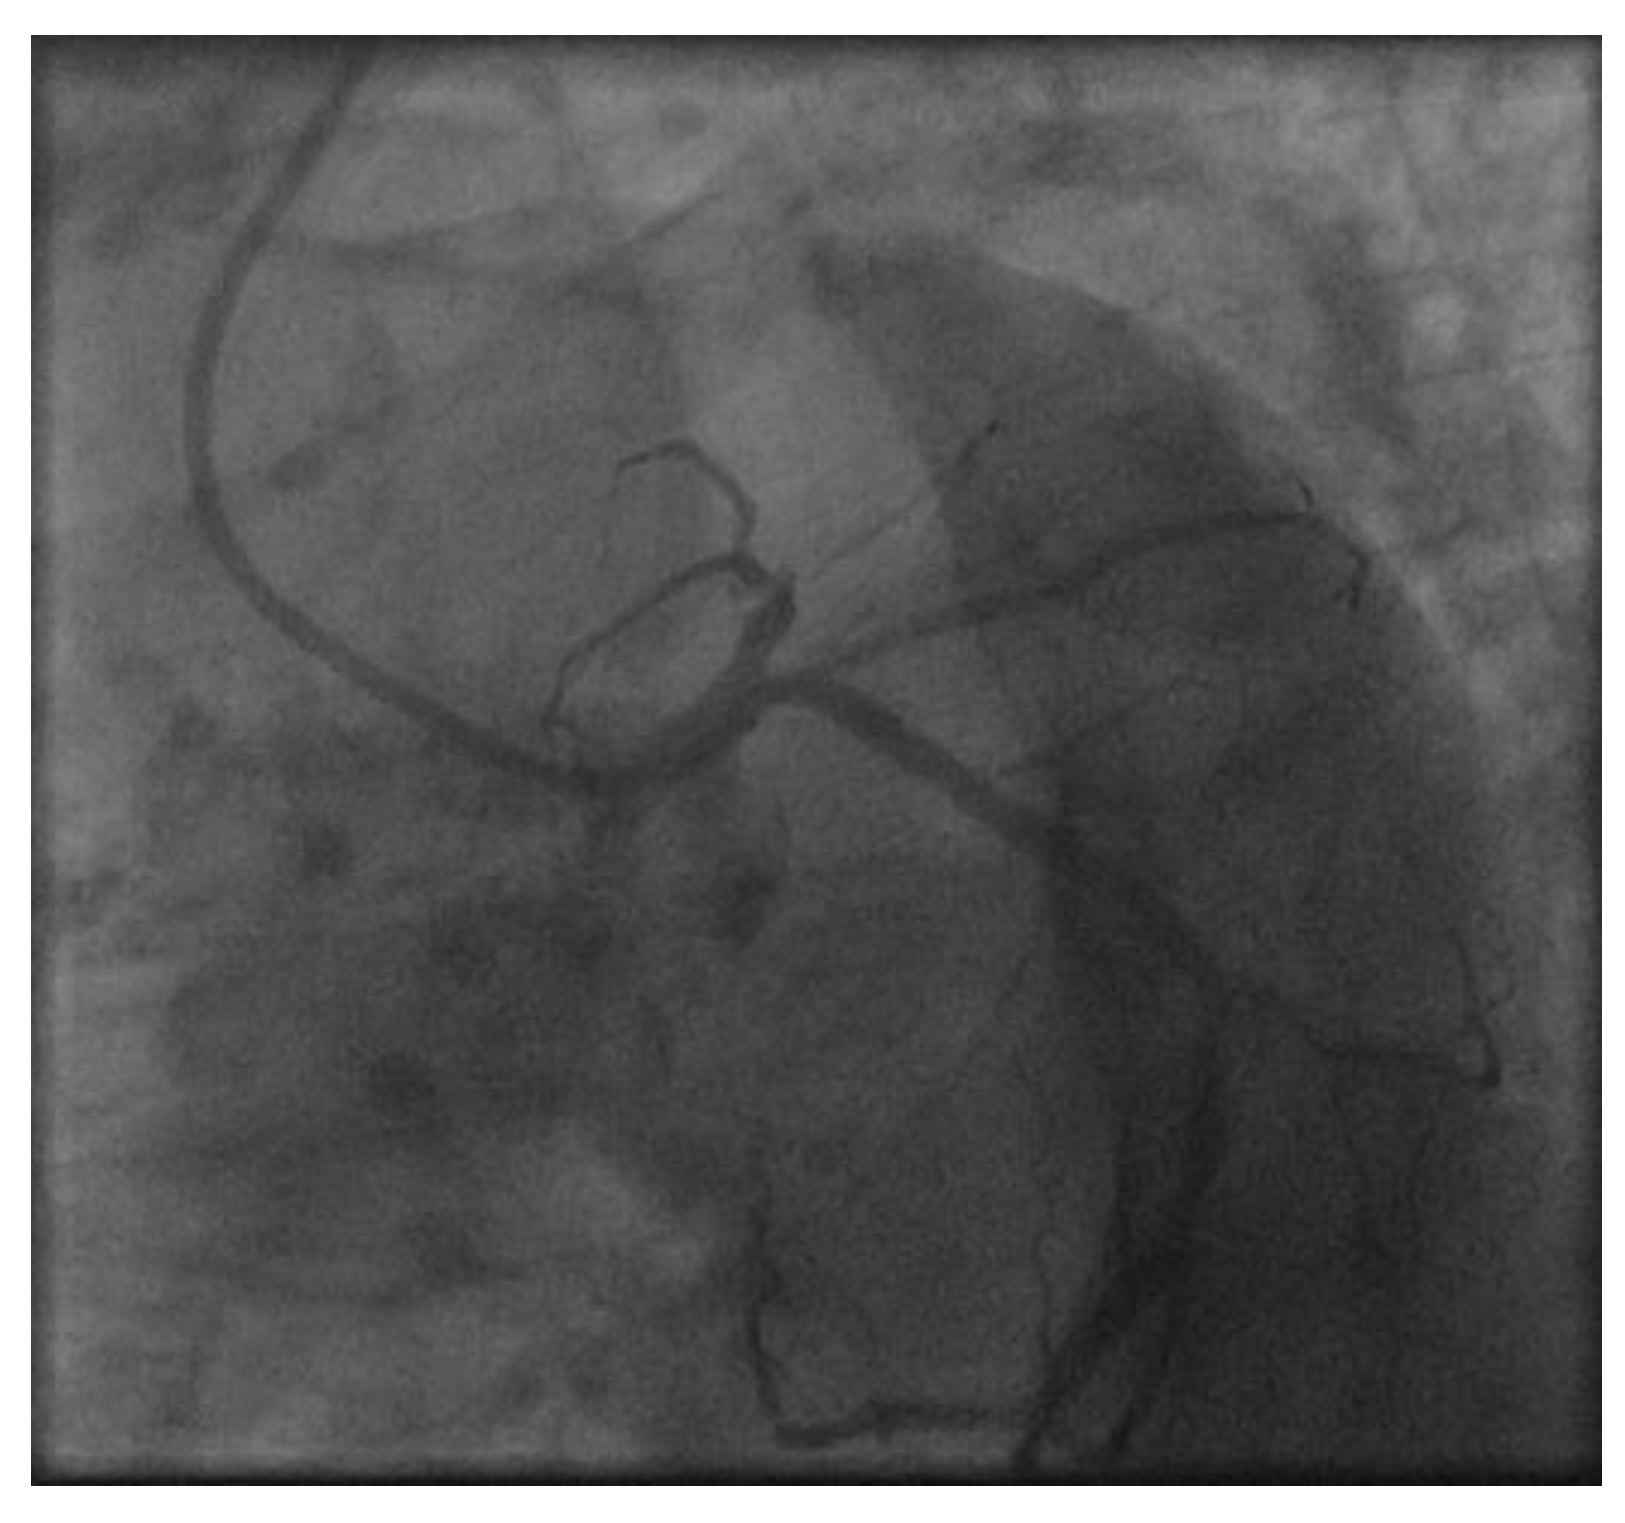

Appendix A.1. Patient A. Male, 46 Years

Appendix A.2. Patient B. Male, 45 Years